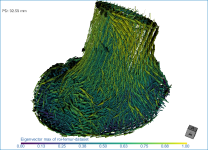

This section of the proximal femur tutorial describes how to compute high-resolution anisotropy maps in different orientations. You should note that when computing high-resolution maps, you should limit the volume of operation to regions that enclose only part of the region of interest. This can be done by creating a series of boxes that describe a particular orientation.

The images below (from left to right) correspond to XZ, XY, and oblique orientations. The computed vector fields are colored by magnitude.

High-definition vector field-based surface anisotropy maps